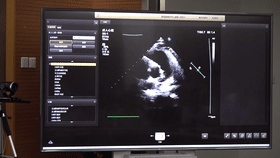

5G远程会诊现场,西安国际医学中心心内科张卫泽主任、超声科陈姗姗主任打开4K高清显示器,屏幕上立刻出现了商洛国际医学中心的B超画面,一位医生正在为患者做心脏B超,随着探头的转动,超声机器上的画面清晰可见,虽然两家医院相距一百多公里,但画面流畅,没一点拖沓。

“真的太棒了”张卫泽表示,“没有延时与卡顿,清晰的好像在一个房间内进行病历讨论”。陈姗姗非常兴奋,直呼很震撼。她告诉笔者,“以前做远程会诊,经常遇到画面和声音不在一个频道、画面模糊等情况,遇到疑难病历只能将影像拷下来回去研究,现在好了这些问题都将一次性解决。”